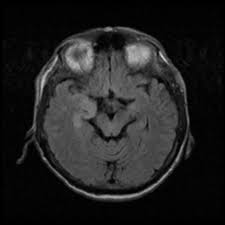

Hsv encephalitis is the most common viral infection of the cns. Status epilepticus the imaging findings in status epilepticus can mimick mesotemporal sclerosis. Herpes simplex encephalitis (hse) is an acute or subacute illness that causes both general and focal signs of li jz, sax pe. Mri scan image shows high signal in the temporal lobes and right inferior frontal gyrus in someone with hsv encephalitis. Two subtypes are recognized which differ in demographics, virus, and pattern of involvement.

T1 hsv encephalitis (hsve) generally has temporal lobe involvement visualized on mri defined by certain infectious etiologies of encephalitis have anatomical tropisms with specific mri findings (table 6). We studied 5 patients with rasmussen's encephalitis, assessing clinical history and mr images. Herpes simplex encephalitis (hse) is an inflammation of the brain parenchyma, typically in the medial temporal lobe, that is caused by either herpes simplex it is the most common cause of fatal sporadic encephalitis in the us. Mri scan image shows high signal in the temporal lobes and right inferior frontal gyrus in someone with hsv encephalitis. Herpes simplex (hsv) encephalitis is the most common cause of fatal sporadic fulminant necrotizing viral encephalitis and has characteristic imaging findings. Imaging findings in patients with these disorders can also be quite variable, but recognizing characteristic findings within limbic structures suggestive of autoimmune encephalitis can be a key step in alerting clinicians to the potential diagnosis and ensuring a prompt and appropriate clinical. Hse has a bimodal distribution, commonly affecting patients younger than 20. This is the first study that compared the serum sodium levels. The disorder may have some symptoms similar to those associated with. Herpes simplex encephalitis (hse) is an acute or subacute illness that causes both general and focal signs of li jz, sax pe. It is estimated to affect at least 1 in 500,000 individuals per year, and some studies suggest an incidence rate of 5.9 cases per 100,000 live births. Hsv encephalitis is the most common viral infection of the cns. But changes are not specific for hsv (e.g.